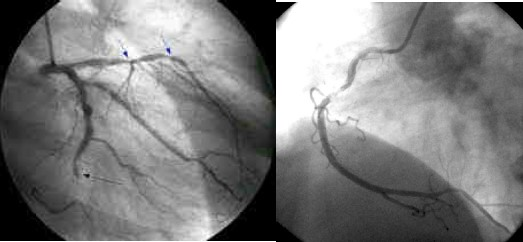

A paciente foi então encaminhada para cineangiocoronariografia, que mostrou os achados representados na figura 2.

Fig. 2